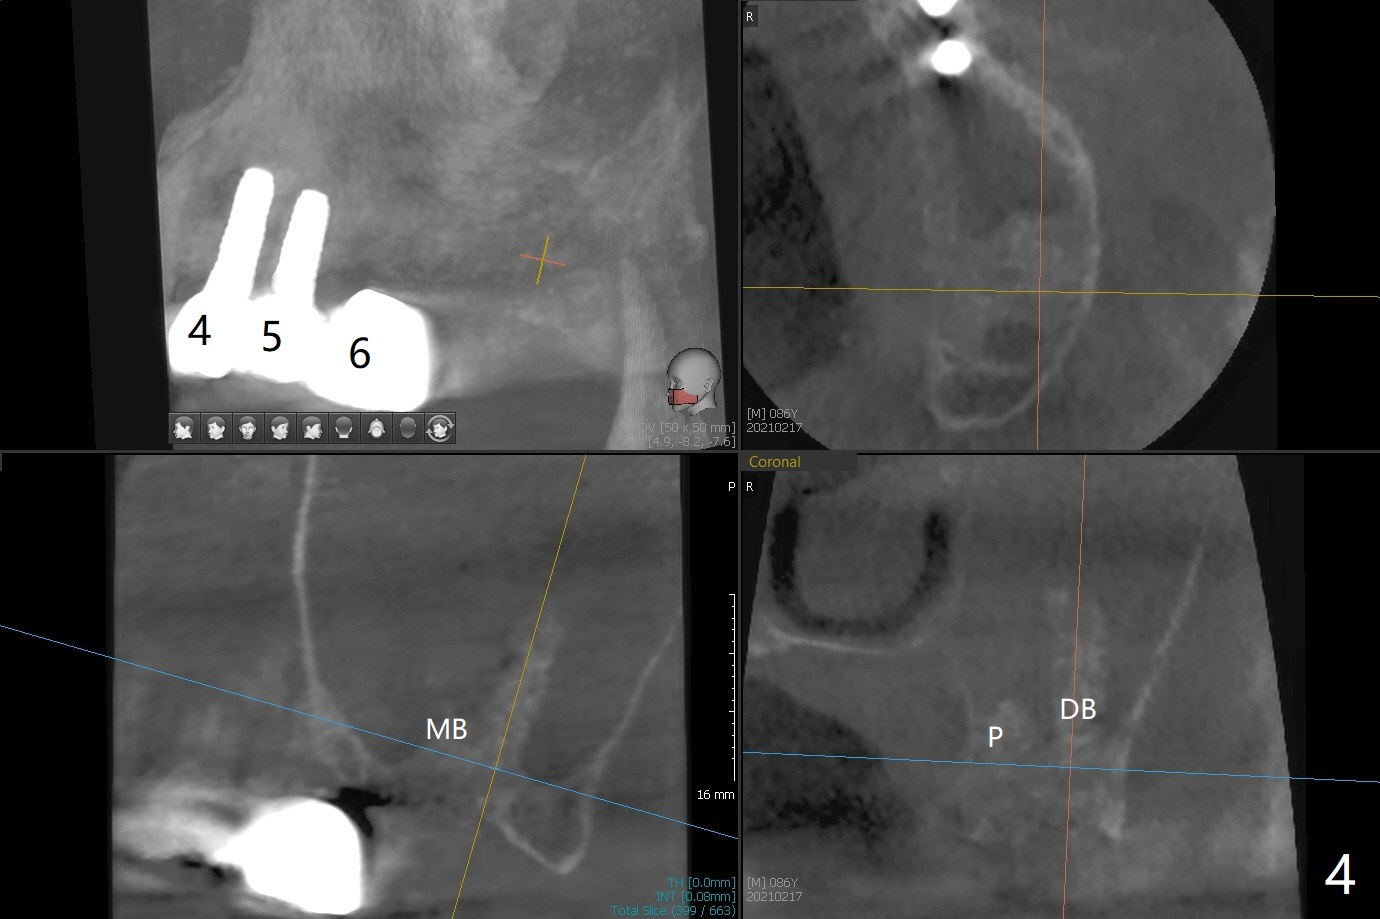

86岁男左上7折裂(图一),要求拔除,经过讨论(7拔除后,4-6悬臂桥可能断裂,对植体产生创伤,图二(左下7存在)),同意植骨。拔牙时发现中隔特别粗大(图三,五:S),三个牙槽窝根尖好像在中隔下面相互交通,擤鼻涕却没有气泡,仿佛与上颌窦没有相通。艰难清创后,放置Vanilla骨粉(图三),腭侧根特别容易填满,而颊侧根填入许多骨粉,术后CT远中颊侧骨粉尤其多(图四),上颌窦粘膜增厚(原来有季节性过敏)。术前根尖片显示远中颊侧根尖周围阴影很长(图五,六(虚线))。第二天早上鼻出血(仅有一次),今后牙槽窝明显比牙根长,清创控制深度,先放置胶原塞或PRF膜,后放骨粉。病人已经购买水牙线。术后7天树脂敷料稳定,局部卫生好(图七),骨粉好像进入上颌窦后部(图八)。术后1.5个月树脂敷料仍在原位,很容易撤除,牙槽窝愈合(图九),骨粉好像没有丢失(图十)。